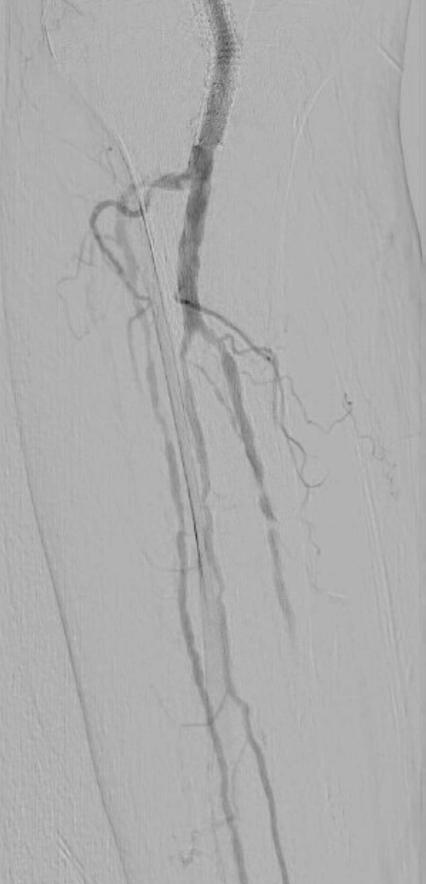

A 75-year-old female patient with diabetes and end-stage kidney disease (ESKD) presented with progressive right second toe swelling ulceration with gangrene and rest pain (Figure 1). There was extensive osteomyelitis and underlying tissue injury which required a planned amputation of the second toe. We were consulted prior to amputation for angiography, which demonstrated patent inflow vessels but severe BTK tibial disease. The baseline angiogram is shown in Figure 2. There was no inline flow to the foot, with occlusion of the anterior tibial, posterior tibial and peroneal arteries (Figure 2a). There was reconstitution of the peroneal artery, with partial filling of the posterior circulation via the posterior communicating artery. There was reconstitution of the anterior circulation with a visible small dorsalis pedis artery (Figure 2b).

Procedural overview

Given the angiosome of the tissue loss, we elected to pursue opening the anterior tibial CTO. Access with a 5F, 70cm sheath was used from a contralateral femoral approach. Using a 0.014” microcatheter and wire escalation, we were able to cross into the true distal lumen of the distal anterior tibial circulation using a 12-gram tipped guidewire (Figure 3a). A 2.5mm Shockwave E8 was used for multiple treatments along the entire length of the CTO segment (Figures 3b, 3c). Post IVL therapy, angiography showed brisk flow through the anterior tibial and into the distal anterior circulation of the foot (Figures 4a-c). This improvement in circulation allowed for this patient to undergo her planned second toe amputation with primary close (Figure 4d).